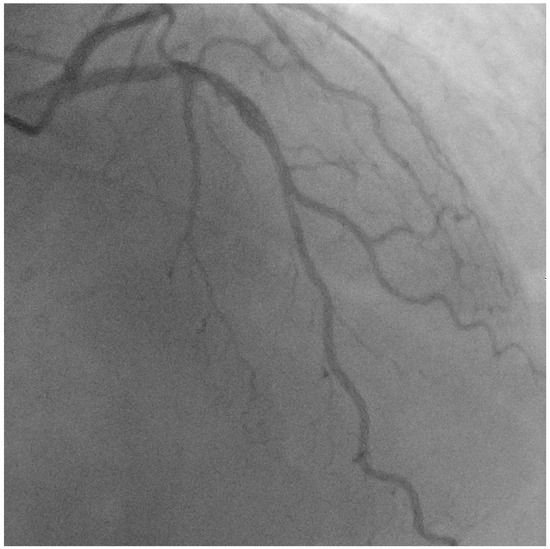

- Case # 3

| Case 3 | 41 yo | LAD/D1 | LAD stent, D1 balloon | 11 years | 11 y, NR |

| Case 3 | LAD ISR | D1 is patent |